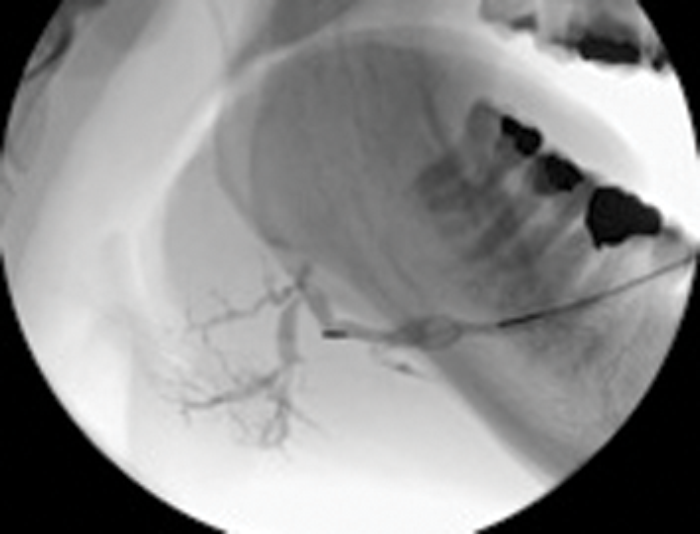

Figure 3: (A) The preoperative sialogram identifying a stone in the middle third of the submandibular duct.

Figure 3: (B) The insertion of a Dormia basket (closed).

Figure 3: (C) The stone trapped in the open basket.

Treatment of salivary calculi by interventional sialography

Miniature Dormia baskets can be inserted into the major salivary ducts under x-ray or ultrasound guidance and manipulated to pass and grasp small stones. The procedure is performed under local anaesthesia (by direct infiltration of the buccal oral mucosa or inferior dental nerve block). The trapped stone is then withdrawn to the duct ostium, where a small relieving papillotomy incision may be needed to release the stone. It is important to maintain regular salivary flow through a papillotomy site, if this has been necessary to release a stone during extraction in a Dormia basket, in order to prevent healing over of the duct orifice. This may be done by prescribing regular hydration and use of sialogogues, assisted by gland massage.

Case selection is best performed on the basis of preoperative sialography. Ideally the stone should be within the main extraglandular duct, mobile and no more than 20-25% wider than the distal duct running from stone to ostium [12].

Duct strictures lying between the stone and duct orifice may require dilatation by balloon ductoplasty but should always be viewed with caution as they are invariably densely fibrotic and may still impede stone removal.

Success in clearance of stones using Dormia baskets is reported to range from 60-100%. This technique therefore offers a simple, effective, highly non-invasive cure which is achievable in one visit with minimal morbidity. In avoiding general anaesthesia it offers treatment options to patients with other more serious co-morbidities.